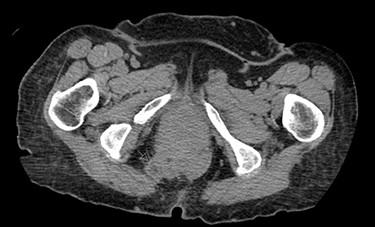

Once the hernia was completely reduced, the hernia sac was resected. The muscular defect of the pelvic floor was delineated. The pelvic floor was reconstructed, and the muscular defect was reapproximated from lateral to medial using 3-0 V-Loc running sutures in a tension-free manner. An 8 × 8 cm synthetic bioabsorbable Phasix mesh was used to reinforce the repair (Fig. 3). To prevent the rectum from falling back into the pelvis, a suture rectopexy was performed in the traditional fashion by clearing the sacral promontory from overlying soft tissue, exposing the periosteum of the sacral promontory and using silk sutures to attach the rectum to the sacrum. The pelvis was reperitonealized using running 3-0 V Loc absorbable sutures. Post-operatively, the patient had return of bowel function, adequate pain control, tolerated a soft diet and was discharged after 2 days. The patient had significant improvement in her fecal incontinence at her 4-week follow up visit, and post-operative CT demonstrated resolution of the hernia (Fig. 4).

Post-operative CT demonstrating mild fluid in pelvis and resolution of the hernia (black arrow).